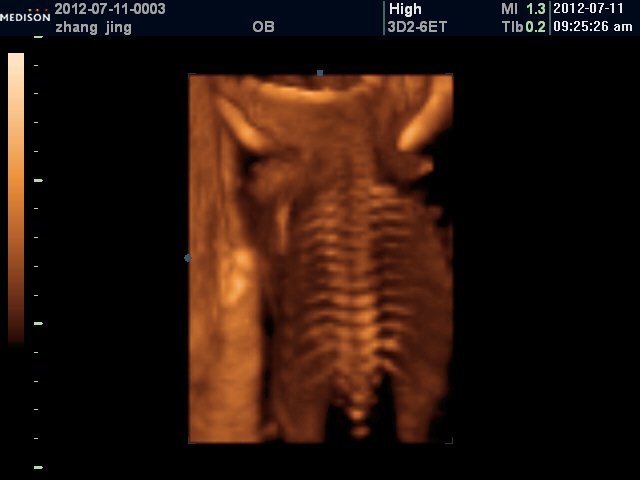

患者信息:女 28岁 陕西 西安 病情描述(发病时间、主要症状等):具体的:左侧脑室后角1.2cm, 右侧未探及, 羊水最大深度7.8cm,羊水指数24.4cm,双顶径6.9cm,下肢可显示,脊柱连续想得到怎样的帮助:是不是胎儿有问题啊?说什么可能脑积水,脊柱裂,……记不得了,让过个月去再查4维。有没有什么更好的办法赶紧检查出来呢?曾经治疗情况及是否有过敏、遗传病史:无遗传史,有点贫血